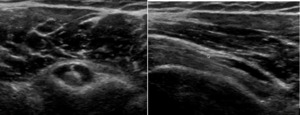

Figure 3.

3a: Effusion and edema are seen as an area of hypoechoic signal within the tendon sheath surrounding the LHB tendon. The anechoic ring is known as a “halo sign” on a SAX view. This edema could be either a tenosynovitis or a capsulitis. The LAX will be the differential view.

3b: Joint effusion within the tendon sheath seen here on the LAX. On the LAX views, it reveals presence of fluid distally indicating a tenosynovitis. A capsulitis would not show effusion in the biceps tendon sheath distally on the LAX view.